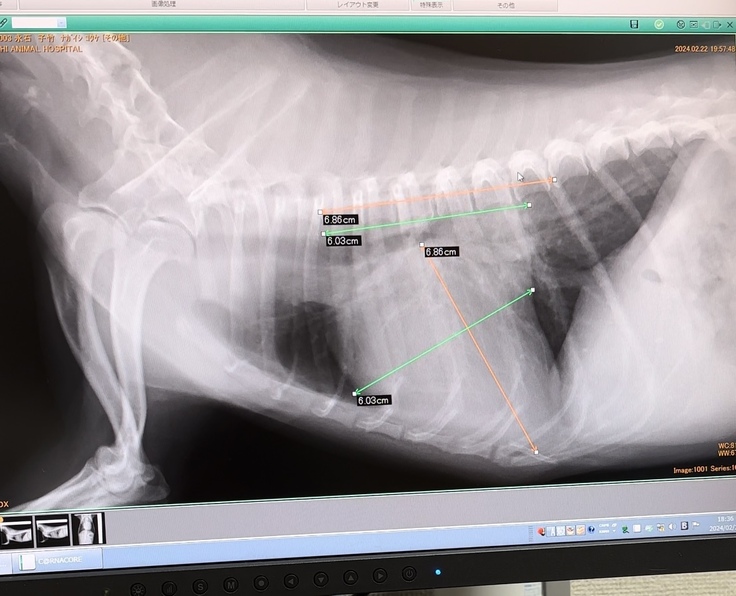

それが2024年2月22日

やはり診断は変わらず「僧帽弁閉鎖不全症」

心臓が肥大してしまっている事により、気管を圧迫している。

心臓もかなり大きくなってきているので、いつまた肺水腫になってもおかしくない状態な為、

手術という方法もあると伺いその日は帰宅。

退院してからは毎週検診に通院し、

エコー検査と必要であればレントゲン、

薬の調整をしてもらっています。